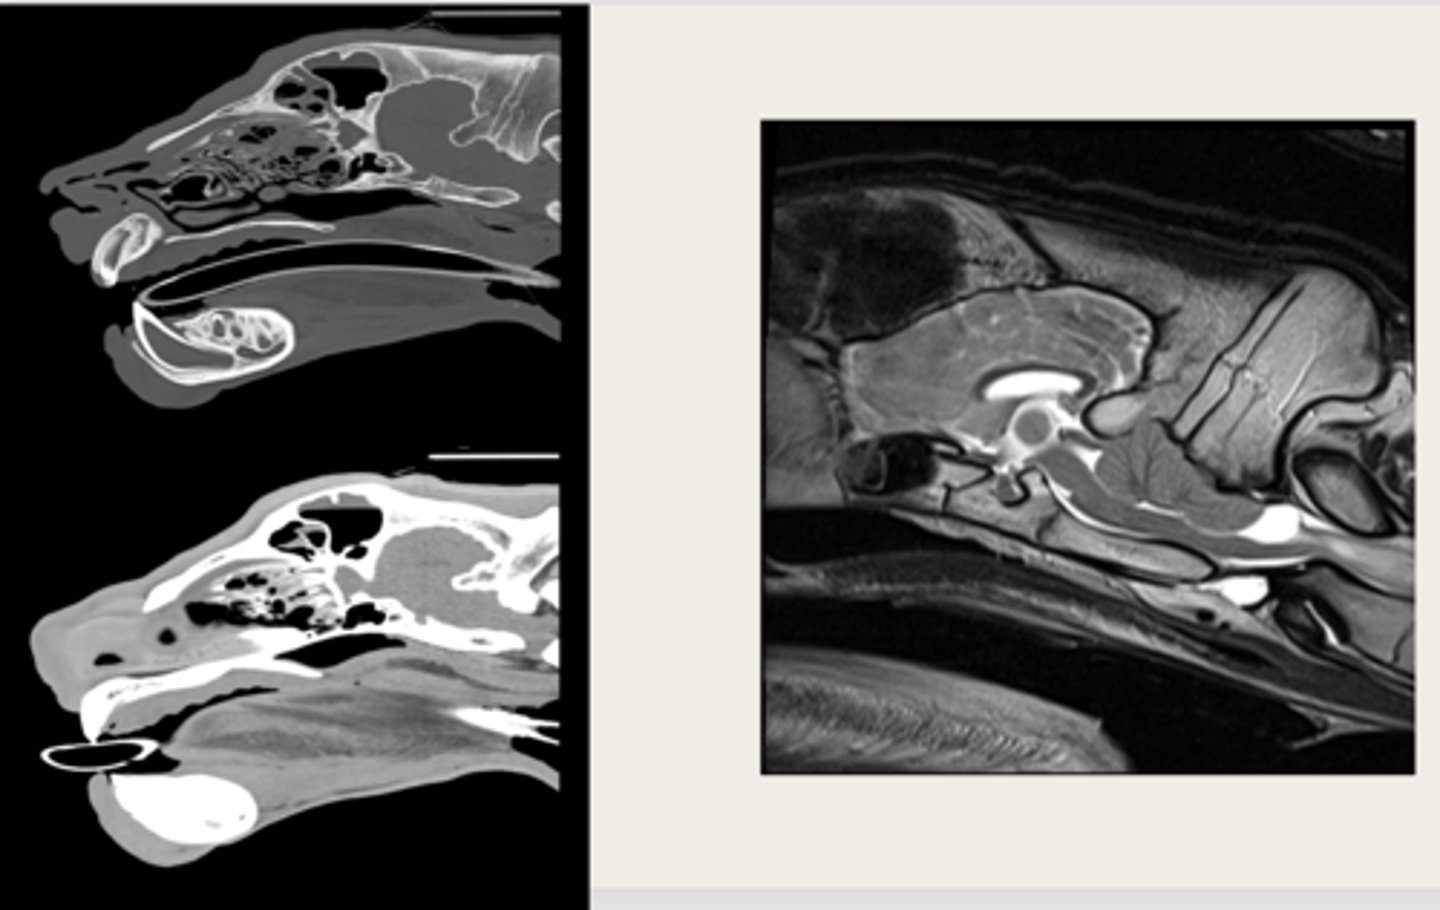

CT

is the left image a CT or MRI?

left- CT

right- MRI

which images are CT and which are MRI?

-cross sectional

-same area

-TRANSVERSE PLANE

how are these images the same?

right- bright bone

left- less bright bone, more definition in tissue

how are these images different?

left- MRI

right- CT

which one is the CT and which is the MRI?